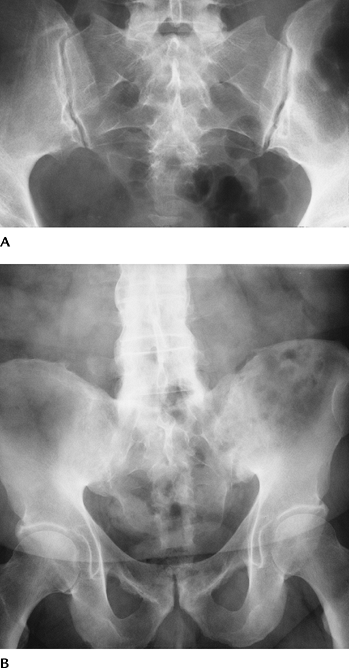

![]() |

FIGURE 4-48 AP radiographs (A,B) demonstrating developmental dysplasia on the right. The acetabular angle (line

along acetabulum to Hilgenreiner line [H]) is increased and the hip is displaced superolaterally with interruption of Shenton line (S) (broken white lines). The femoral head should lie in the inferomedial (im) quadrant. Four quadrants (im, inferomedial; il, inferolateral; sl, superolateral; sm, superomedial) are formed by a line (Perkins line) at the acetabular margin perpendicular to Hilgenreiner line. The femoral head is out of the im quadrant in (B). |